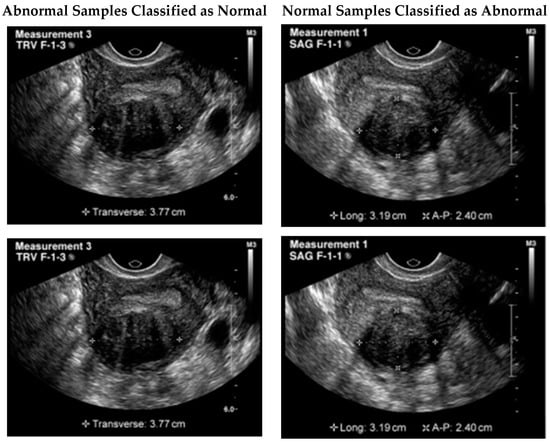

The first step was to obtain the dataset of ultrasound images with UF. In this study, a publicly available dataset from Kaggle was used. The images were preprocessed to remove noise, adjust the contrast, and normalize the intensities. Data collection and preprocessing were crucial steps in the development of DPCNN for automated UF detection in ultrasound images. For this study, the dataset comprised 1057 grayscale images with a size of 256 × 256. To prepare the dataset for use in the DPCNN architecture employed in this study, the grayscale images were converted to RGB format. Following this, the preprocessed dataset was split into training and testing data using an 80/20 split. Before training the model, data augmentation was performed to increase the size of the training dataset and enhance the model’s ability to generalize. Specifically, we applied random transformations such as rotation, zoom, and horizontal/vertical flipping to generate new training images. Figure 3 shows the samples taken from the dataset.

Although the proposed model illustrated remarkable results, still a few samples were wrongly classified. One possible reason for this failure could be the similarity of the tumor to the surrounding tissues. In some cases, fibroids can blend in with the surrounding tissues, making it difficult to differentiate them from healthy tissues. Additionally, the presence of noise or artifacts in the image could also impact the model’s ability to accurately detect the tumor. It is important to note that even experienced human experts can sometimes miss the presence of a tumor in ultrasound images due to these factors. Therefore, improving the model’s robustness to noise and artifacts could potentially improve its performance in detecting these types of failure cases. Figure 6 illustrates a few of the misclassified test samples.

Figure 3. Sample ultrasound images from the dataset.

Figure 6. Misclassified test samples.